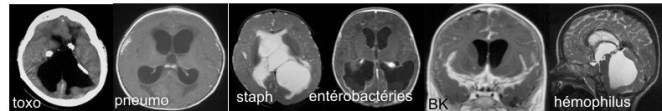

bactériologie

- dans nos contrées, l’hémophilus est devenu exceptionnel, le pneumocoque persiste malgré la vaccination, le méningocoque reste peu fréquent.

- dans les pays en voie de développement et émergents, mais également dans nos pays, le BK reste une cause possible

- chez le nouveau-né, on rencontre le streptocoque B d’origine materno-foetale, les entérobactéries, et les staphylocoques qui compliquent les séjours prolongés en réanimation.

- en anténatal, la toxoplasmose provoque une atteinte neurologique d’autant plus grave qu’elle s’associe à une atteinte rétinienne